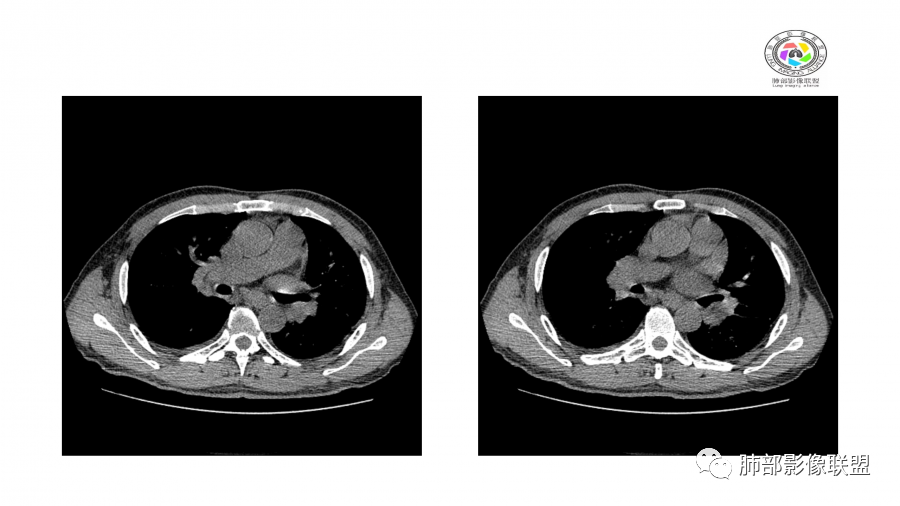

南边:

边界模糊,距离胸膜有间隙,内部支气管通畅

一月后:

病灶此起彼伏